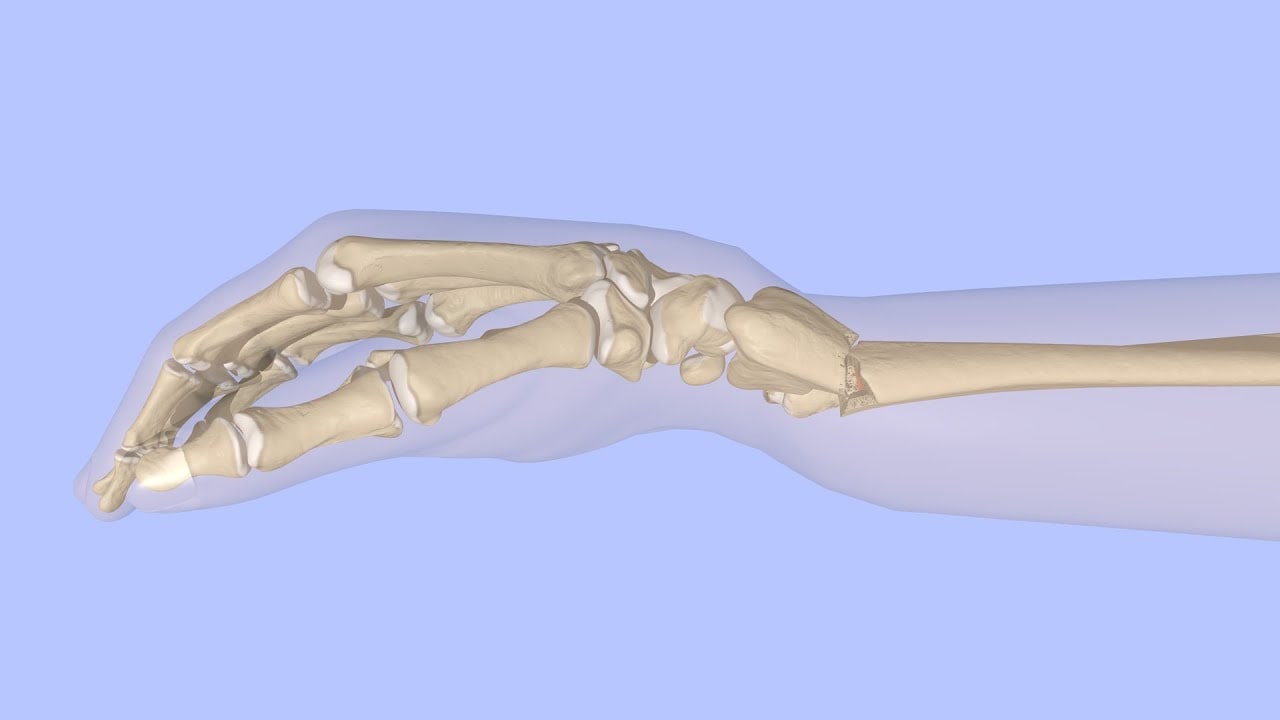

Артроскопия – это инновационный способ диагностики, который позволяет более точно оценить изменения, происходящие в тканях организма при травмах. Результаты исследований, полученных таким методом, оказываются намного точнее, чем при МРТ или УЗИ. При этом артроскопия, как метод малоинвазивного вмешательства, при проведении хирургических операций позволяет сохранить целостность ткани вокруг суставов.

Ведущие немецкие доктора - Профессор Габор Салай и доктор Александр Шютц выступят с докладами об эндоскопическом релизе карпального канала, инновационных техниках хирургии кисти – Arthrex, а также осветят вопросы восстановления триангулярного фиброзно-хрящевого комплекса при помощи направителя TFCC Wrist Drill Guide, поделятся опытом реконструкции ладьевидно-полулунной связки, продемонстрируют, как с использованием системы фиксации CMC TightRope стабилизировать пястно-запястный сустав при ризартрозе трапецевидной кости.

В рамках семинара также состоится мастер-класс «Живая Хирургия», в ходе которого специалисты продемонстрируют хирургические техники малоинвазивной и артроскопической хирургии кисти и кистевого сустава на примерах трех клинических случаев.